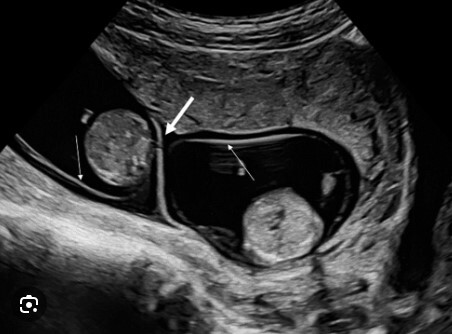

What type of twin pregnancy?

Dichorionic diamniotic

Note: Arrow point to the twin peak sign (beak-like tongue between the two membranes of a dichorionic pregnancy).